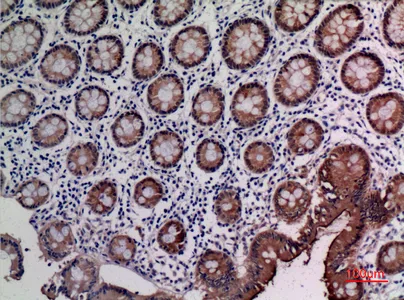

CD66e Rabbit Polyclonal Antibody

Cat: APRab08434

Size1:50μl Price1:$118

Size2:100μl Price2:$220

Size3:500μl Price3:$980

Size2:100μl Price2:$220

Size3:500μl Price3:$980